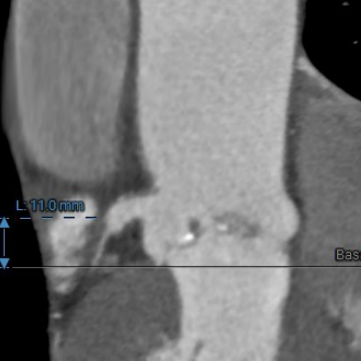

左冠开口高度:

11mm

● 主动脉根部:患者主动脉瓣为三叶瓣,左右冠窦可见部分粘连,重度钙化,瓣环到LVOT层面可见钙化,法式窦结构较大,左冠开口高度约11.0mm,右冠开口高度约16.2mm,STJ高度约19.5mm,直径约28.1mm,升主动脉未见明显扩张,心脏角度约49°,左室形态稍小,心肌增厚。